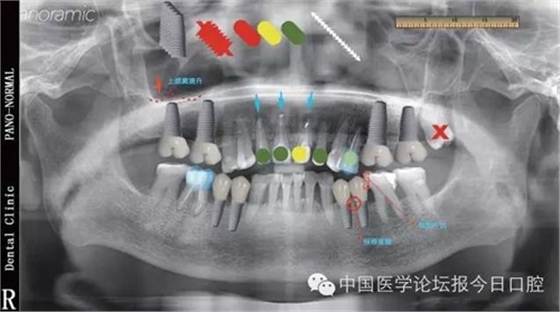

標(biāo)準(zhǔn)化優(yōu)勢在完整的病例書寫中,最主要的內(nèi)容包括主訴、現(xiàn)病史、檢查、診斷、處理等,其中檢查是非常重要的,也是最復(fù)雜的。在DSD模版里,會(huì)有許多不同顏色,不同形狀的圖標(biāo),這些圖標(biāo)是實(shí)現(xiàn)平臺(tái)標(biāo)準(zhǔn)化的重要工具。

比如在模版中的“圓點(diǎn)”可以有紅色、黃色、綠色等不同顏色,可以把紅色的“圓點(diǎn)”定義為必須拔除的牙齒,綠色“圓點(diǎn)”定義為保留的牙齒,黃色“圓點(diǎn)”定義為介于二者之間的情況;同理,需要根管治療的,需要牙周手術(shù)、種植、正畸牽引的牙齒,我們都可以通過特定顏色,特定形狀的符號(hào)進(jìn)行標(biāo)注,這樣不僅用一張圖就可以基本涵蓋患者的所有信息,而且避免了文字記錄過多引起的理解上的混亂及不清晰的弊端。